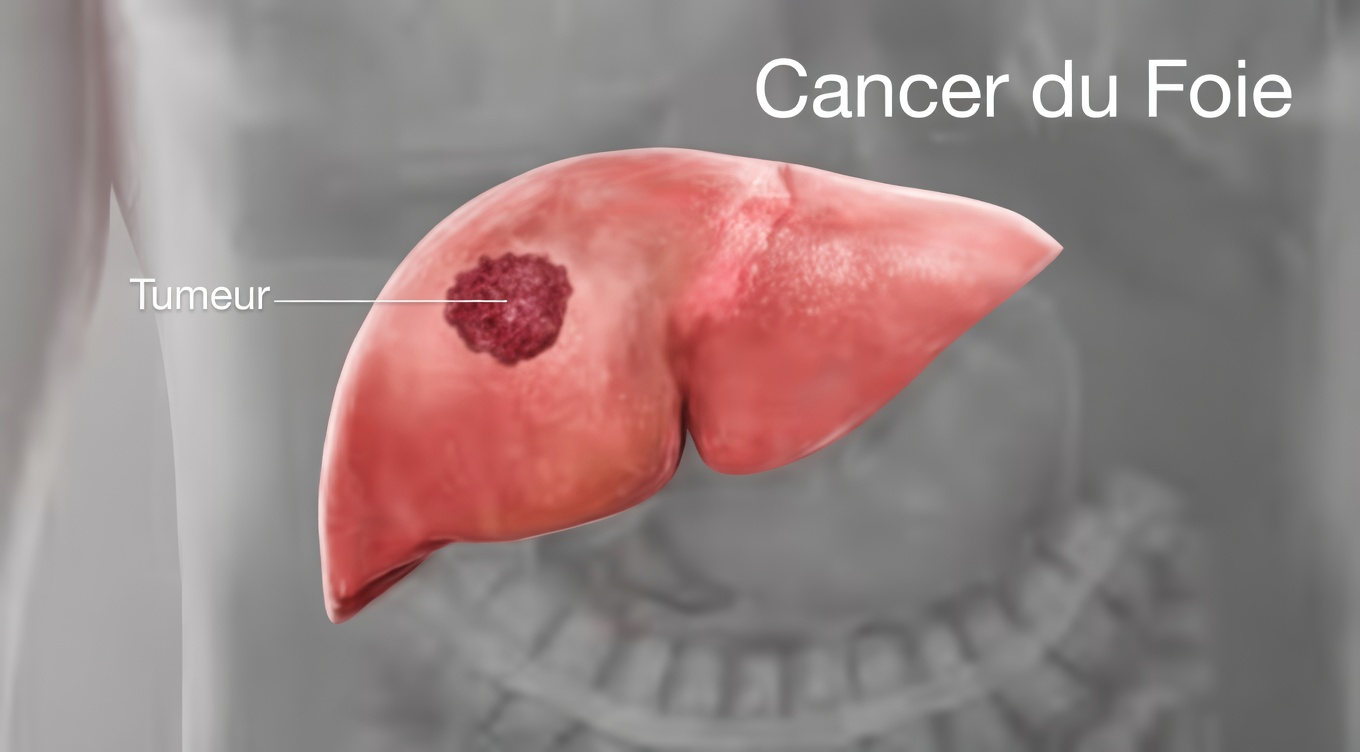

L’habitude quotidienne la plus puissante pour protéger votre foie

Parmi toutes les habitudes qui soutiennent la santé du foie, une se distingue nettement : réduire drastiquement, voire supprimer totalement la consommation d’alcool.

L’alcool est l’un des principaux facteurs de dommage hépatique au niveau mondial. Même pour une personne sans cirrhose, sa consommation régulière surcharge le foie. Lorsque des signes de cirrhose du foie sont déjà présents ou suspectés, chaque verre supplémentaire augmente le risque de progression vers des complications graves.

Si vous reconnaissez plusieurs de ces signes de cirrhose du foie, n’attendez pas : prenez rendez-vous avec un professionnel de santé pour un bilan complet. Plus la cirrhose est détectée tôt, plus il est possible d’agir et de protéger durablement votre foie. Votre corps vous envoie des signaux : les écouter est déjà un grand pas vers la guérison.